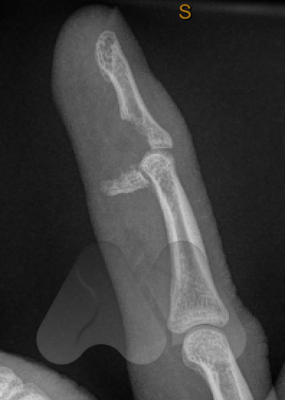

A jersey finger is when the flexor tendon that bends the fingertip, pulls off the bone, you may feel a “pop”. It is often caused by a forced and rapid extension of a clenched hand. It results in sudden pain and an inability to bend the fingertip and can cause bruising, pain and swelling down the length of the finger.